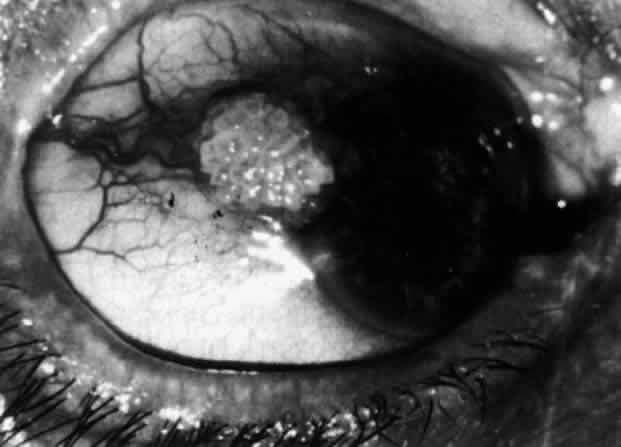

Scleritis usually affects the anterior segment of the eye, possibly because this is the area with the best blood supply, but with sluggish flow through the vessels (Fig. 19). The sclera is thickened and roughened in the affected area, which appears to be sharply demarcated from the rest of the sclera. However, tissue obtained at surgery during the course of grafting of areas adjacent to necrotic tissue shows marked pathologic changes.20,21 The area of affected sclera may be swollen, excavated, or frankly ulcerated with undermined edges covered with a thin layer of fibrous tissue. However, spontaneous perforation is extremely unusual and, where seen in pathologic specimens, has usually occurred at the time of removal of the eye. A posterior scleritis often occurs as an extension of anterior disease; but, as in Figure 20, most of the inflammation (in some cases all of the inflammation) is in the posterior segment and the exudative detachments and subretinal granulomas can be mistaken for malignant melanoma.

Fig. 20. Posterior scleritis. This eye was removed because of loss of vision and pain, mistakenly diagnosed as malignant melanoma. (Courtesy of Professor N. Ashton)